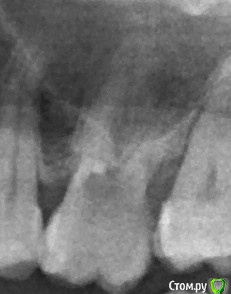

Shelly2000 Опубликовано 18 июля, 2017 Поделиться Опубликовано 18 июля, 2017 Здравствуйте! Вскрывался шестой зуб слева вверху по причине боли при кусании. Через какое-то время обработки изнутри зуба пошла кровь. Врач что-то брызгал внутрь, останавливал кровь, было неприятное ощущение в носу. Снимок сделан после этого. Было подозрение на перфорацию.Врач на снимке перфорацию не увидел. В другой клинике врач посмотрел этот же снимок, сказал, что перфорация есть.Хочется понять, кто из них прав. Видно перфорацию на снимке или нет? Спасибо за внимание! Ссылка на комментарий

dok1 Опубликовано 19 июля, 2017 Поделиться Опубликовано 19 июля, 2017 Дефект находится внутри полости зуба, окружён стенками. На снимке будет обязательно наложение корней и других элементов, свойственных строению зубов данной групповой принадлежности. + с зубом поработали бором. Дабы исключить ложные признаки вероятной перфорации и требуется "взгляд изнутри". Если при зондировании дна сформированной полости зуба без погружения в каналы начинается кровотечение, то с высокой вероятностью можно говорить о перфорации того самого дна полости. В стоматологии есть много примеров снимков, на которых можно предположить перфорированное дно пульпарной камеры. Но при очном осмотре дефекта не выявлялось. 2 Ссылка на комментарий

dok1 Опубликовано 21 июля, 2017 Поделиться Опубликовано 21 июля, 2017 Любое увеличение всегда лучше его отсутствия. Часто хватает и бинокуляров. На прицельных снимках тоже видно перфорации иной раз. Зависит от условий строения и топографии зуба. В конкретном вашем случае сомнения в обе стороны объективны. Ссылка на комментарий